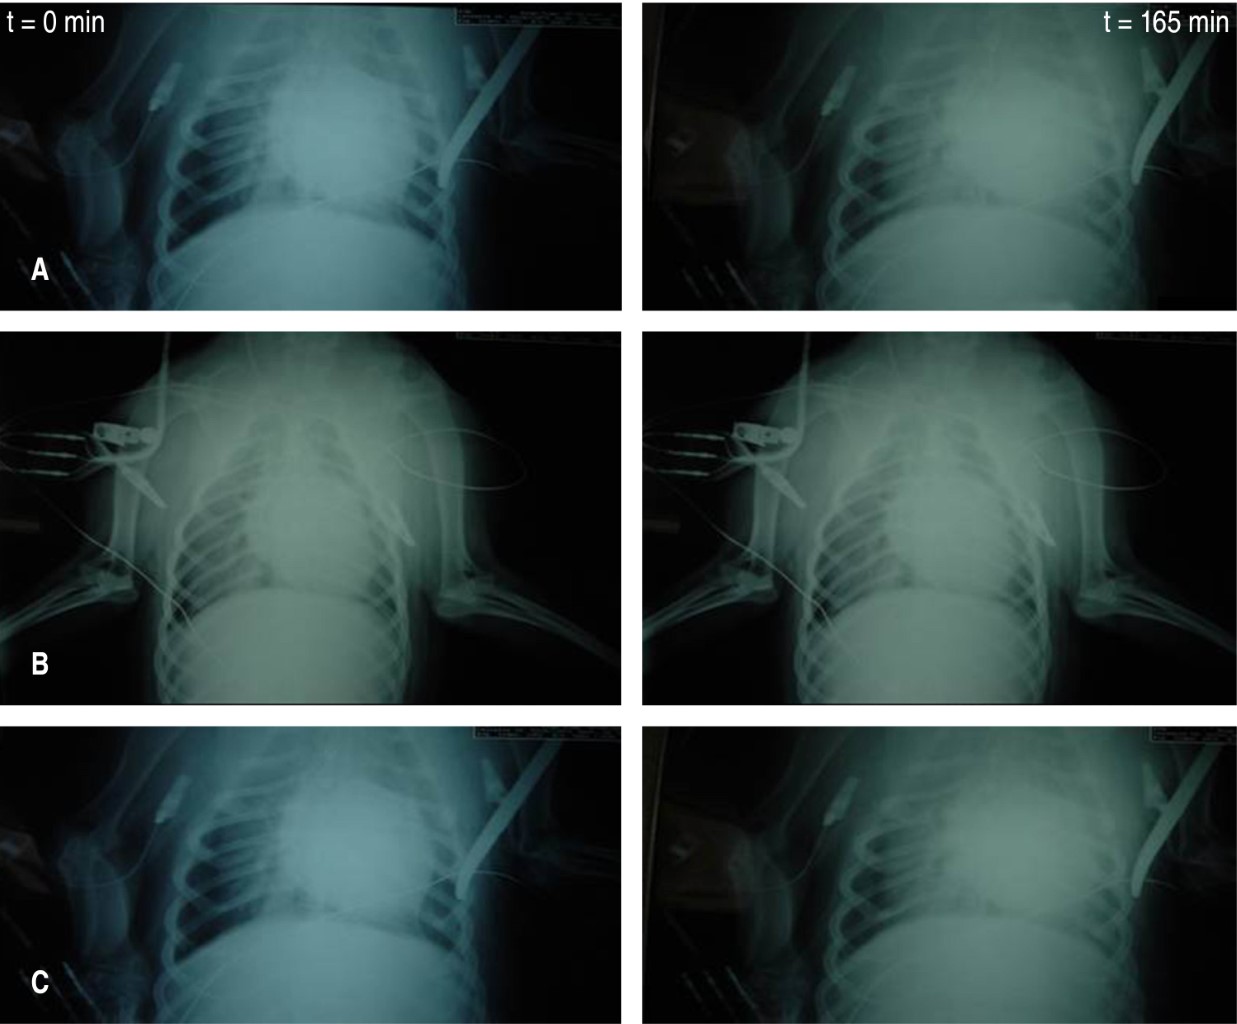

Efecto del pretratamiento con L-arginina en un modelo experimental de síndrome de insuficiencia respiratoria aguda inducido por ácido oleico